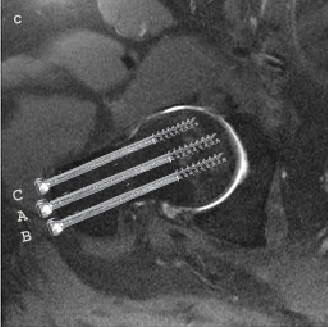

3 Kannulerede skruer (ved fraktur i det skraverede område) Se skrue

placering på billede A og B: